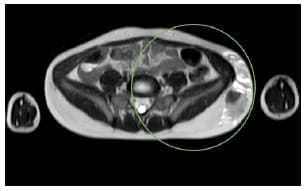

En la resonancia nuclear magnética (RNM) se encontró una masa que deformaba la pared del flanco izquierdo y la pelvis izquierda, con septos intermedios, probablemente relacionado con hematomas (Figura 3).

Figura 3. En la resonancia nuclear magnética se observa una masa que deforma la pared lateral del flanco y el lado izquierdo de la pelvis, de 4 x 9 x 2,8 cm, con niveles líquido- líquido (por sangrado) y septos internos demostrando hematoma en diferentes fases.

Fuente: Imágenes tomadas del registro institucional